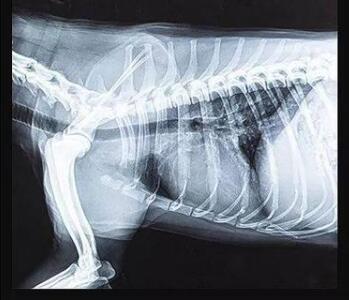

寵物dr專用平板拍攝效果

傳統的平板探測器,相當于普通攝像機,對于拍攝急促呼吸狀態下的寵物,成像效果存在著明顯缺陷。而新一代寵物平板探測器,宛如高速攝像機,能夠清晰記錄動物每一個精準瞬間。